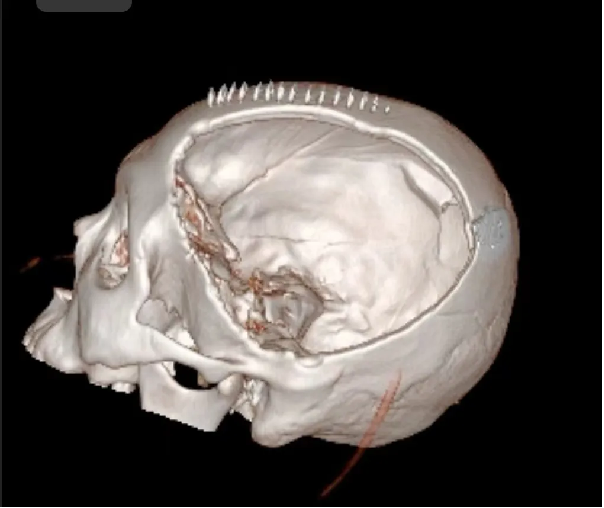

术后: